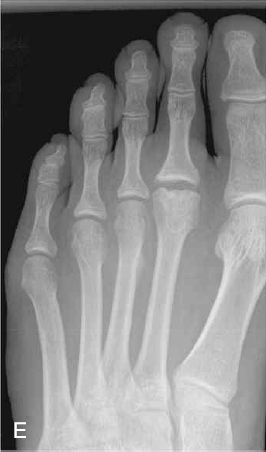

△ E는 Freiberg 병으로, 연골하 피로골절로 인해 제2중족골 또는 제3중족골두의 골괴사를 보인다.